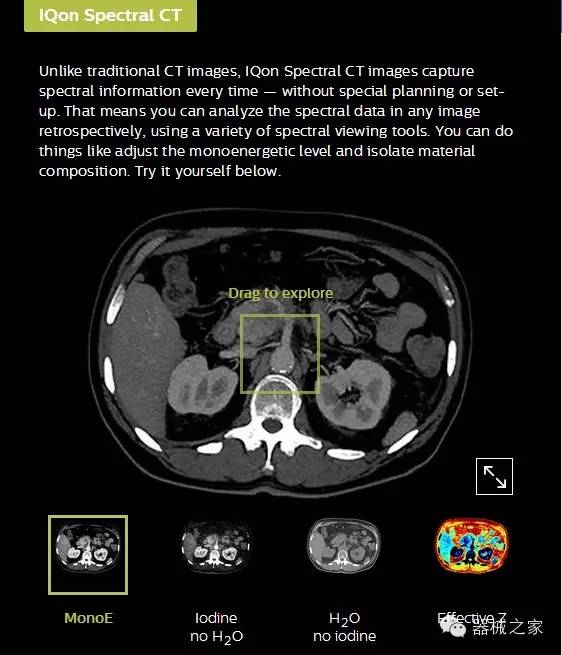

IQon光譜CT能夠按照需求提供光譜量化和工具,并能通過(guò)簡(jiǎn)單工作流程、在低劑量下對(duì)結(jié)構(gòu)進(jìn)行定性分析

IQon光譜CT -- 是業(yè)界首臺(tái)以探測(cè)器為成像基礎(chǔ)的光譜CT,它可以在單次常規(guī)掃描下獲得傳統(tǒng)解剖影像及光譜功能影像。不僅可以提供精準(zhǔn)的診斷信息,還可簡(jiǎn)化工作流程、在低劑量下完成定量與定性分析。